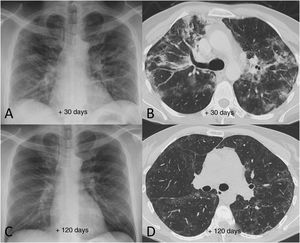

Radiological examples of long-term post-COVID-19 progressionA significant percentage of patients with SARS-CoV-2 pneumonia have radiological abnormalities on the follow-up chest X-ray one month after hospital discharge. In these patients we generally recommend/perform a chest CT without intravenous contrast. In our experience, the severity of the clinical picture usually implies a greater radiological involvement of the lung parenchyma after hospital discharge and a slow favourable response on imaging tests (Fig. 7), especially in patients who required prolonged ICU stays. We do not yet know how much time is needed to establish that the residual radiological findings are stable and definitive. However, some patients with mild or moderate pneumonia may achieve complete resolution of the radiological findings in the first months after discharge (Fig. 8). Ground-glass opacities are among the imaging abnormalities that tend to resolve earlier, while subpleural bands, bronchial dilation and subpleural interstitial involvement usually follow a favourable course that progresses slowly (Figs. 9 and 10). There is, therefore, great variability among patients in the time it takes for residual post-COVID-19 radiological findings to resolve or stabilise. The severity of the clinical picture is probably the most determining factor.

Example of good radiological recovery in terms of chest X-ray and computed tomography findings (lung parenchyma window) in a 45-year-old man with severe SARS-CoV-2 pneumonia after hospital discharge. A and B) Radiological tests 30 days after the onset of symptoms show patchy consolidation along with areas of ground-glass opacification and loss of volume. C and D) Radiological tests 120 days after onset of symptoms show radiological improvement with resolution of the consolidation and a reduction in the extension of the ground-glass opacification, with persistence of slight peripheral reticular interstitial involvement.